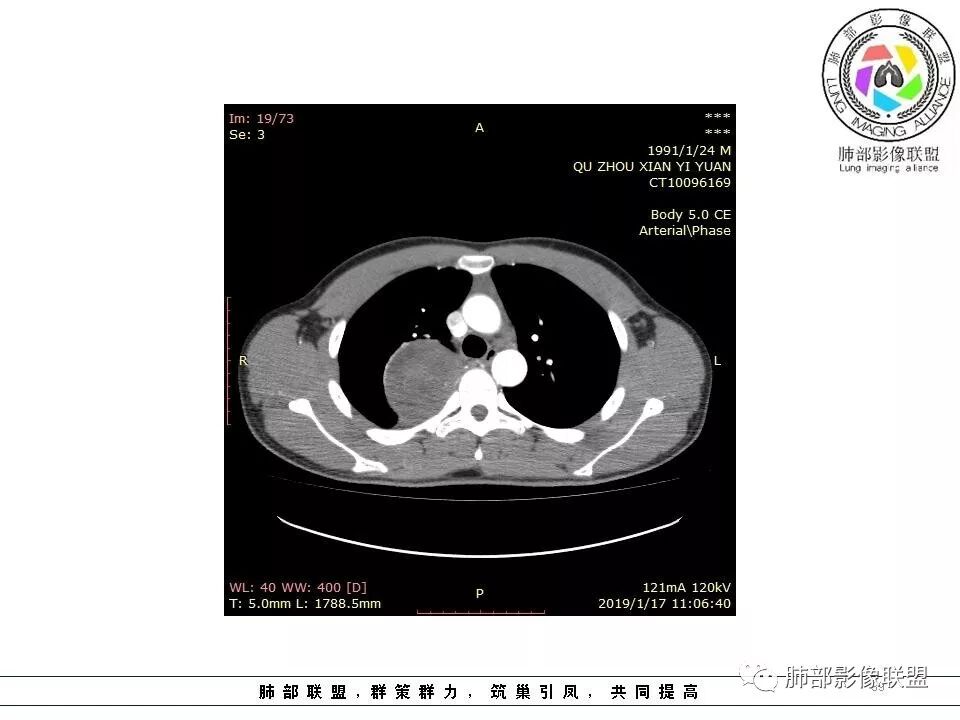

右后纵膈脊柱旁软组织占位,形态规则类圆,边缘光整,肺组织受压,胸膜尾,肋间动脉供血。中度不均匀延迟强化。

后纵隔脊柱旁占位性病变,疾病谱有神经鞘瘤,sft,节细胞瘤,髓外造血。此例有胸膜尾征,蛇纹征 ,延迟强化。考虑胸膜孤立性纤维瘤。看到有供血动脉,但不知道是哪里的血管。

右后纵膈脊柱旁软组织影,与纵隔结构分界不清,形态规则类圆,边缘光整,肺组织受压,胸膜尾,肋间动脉供血。肺动脉推移,中度不均匀延迟强化。考虑神经来源,神经鞘瘤,神经纤维瘤二者不易鉴别。

青年男性,间断胸痛;右侧脊柱旁可见一类圆形软组织密度影,密度欠均匀,增强扫描呈轻中度持续强化,邻近肺组织及肺动脉推移,可见肋间动脉供血,部分胸膜下脂肪可见,部分层面似见与右侧椎间孔相连。考虑后纵隔神经源性肿瘤。

青年男性,右侧脊柱旁软组织肿块,边缘膨隆,密度不均,临近肺组织受压、胸膜增厚,增强后动脉期呈不均匀强化,并可见肋间动脉供血,延迟期强化较均匀,定位肺外,首先考虑SFT,神经源性肿瘤待排

青年男性,胸痛,右上纵膈脊柱旁肿块,形态光整规则,支气管被推移,临近的胸膜明显增厚,有胸膜掀起,增强后密度不均匀,可见蛇形血管征,血供似乎有两根血管供血,考虑SFT

右上肺野脊柱旁软组织肿块,边缘光滑整齐,肺组织及气管右肺上叶支气管受压前移,外移,边缘可见胸膜尾征,病灶内密度不均,增强后渐进性持续强化,其内可见明显蛇纹血管征,首先考虑肺外来源,sft.可能性大

肋间动脉供血,强化尚均匀,逐步强化